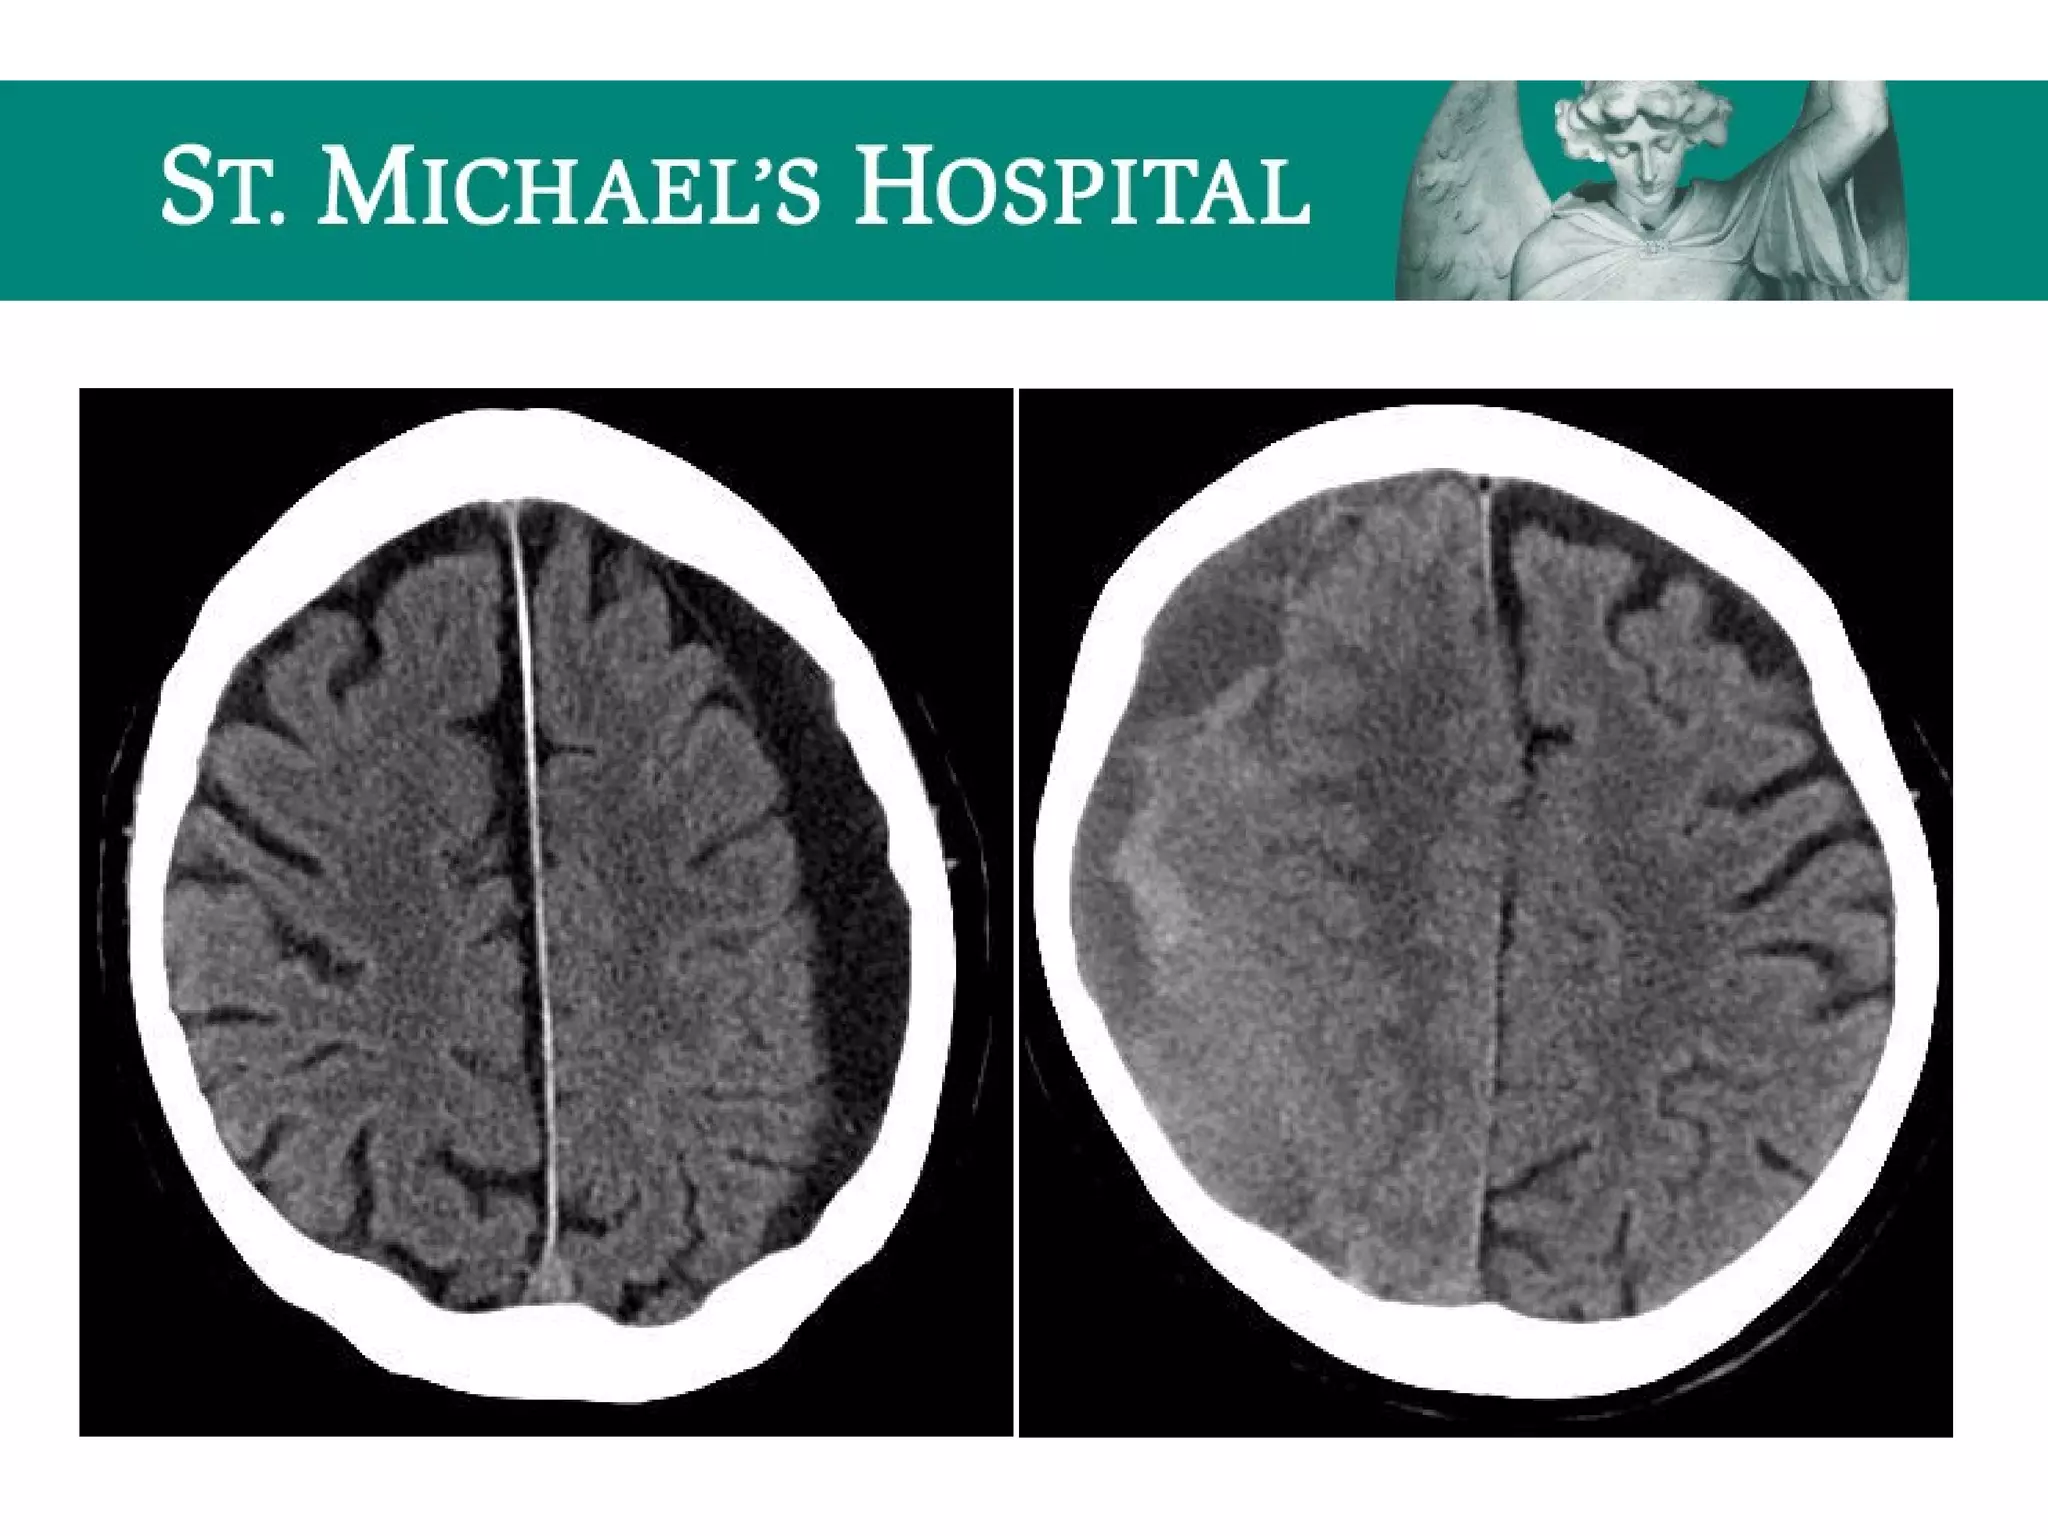

Global Cerebral Ischemia/Anoxic Brain

Injury

 Diffuse brain swelling/edema can result in:

 global loss of gray-white differentiation

 global sulcal/cisternal effacement

 pseudo-subarachnoid hemorrhage

 dense cerebellum

Global Cerebral Ischemia/AnoxicBrain Injury  Diffuse brain swelling/edema can result in:  global loss of gray-white differentiation  global sulcal/cisternal effacement  pseudo-subarachnoid hemorrhage  dense cerebellum